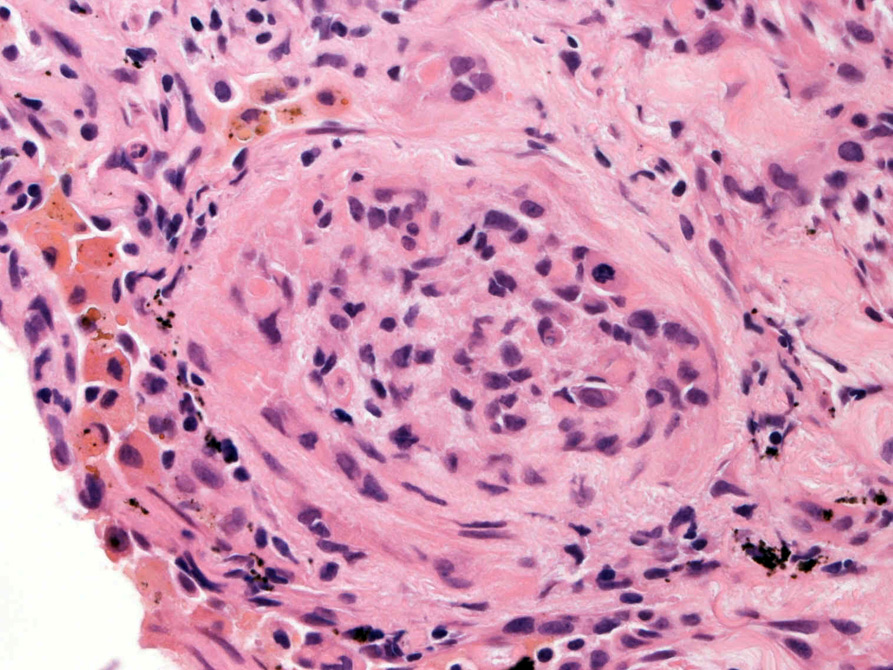

hyperchromaticな類円ないし多角の核で好酸性の広めの細胞質をもつ上皮様細胞が増殖している。右図では血管内を占拠するように腫瘍細胞が認められる。